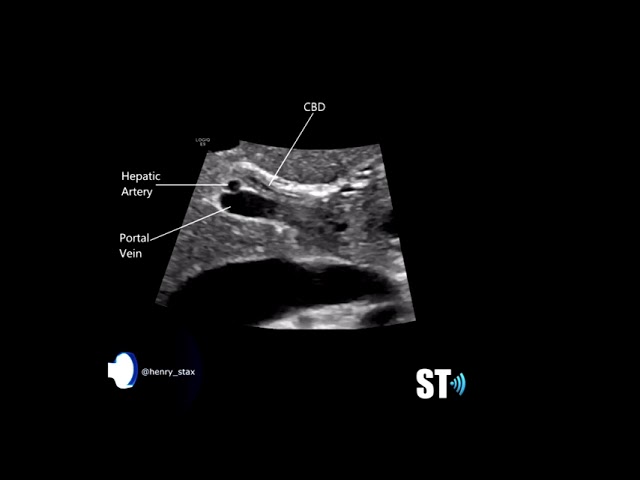

Scanning the Common Bile Duct CBD

June 27th, 2021

Eden Some tips for the cbd. My website: sonographictendencies.com Follow me on instagram at https://www.instagram.com/sonographic_tendencies/ and facebook at https://www.facebook.com/sonotendencies